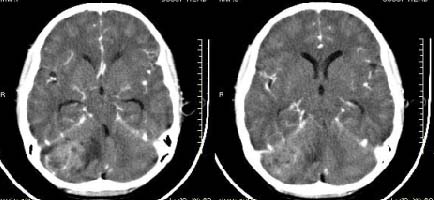

以下是引用子期在2009-6-10 21:34:00的发言:[br]髓母细胞瘤一般位于中线附近和小脑蚓部,该病灶位于右侧小脑半球,倾向于毛细胞型星形细胞瘤,当然也不能完全排除髓母细胞瘤。

以下是引用随光逐影在2009-6-10 22:26:00的发言:[br]考虑右侧小脑胶质瘤,髓母细胞瘤待排。